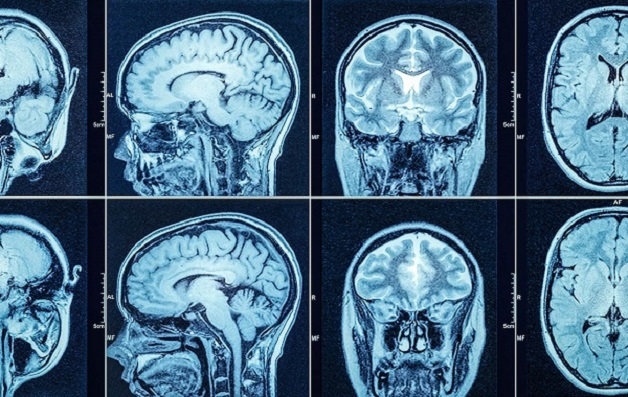

Hình ảnh chụp CT não